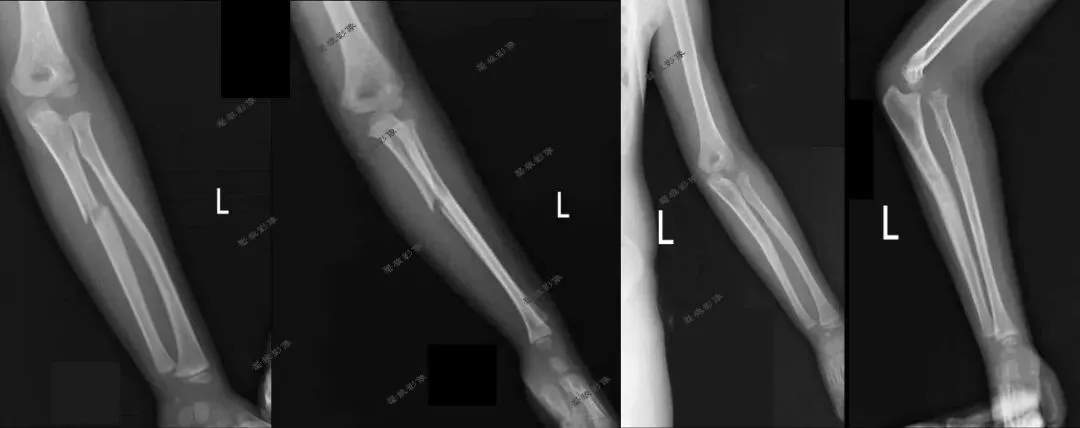

一、先来看几组图片

我们再看肘关节几组图片